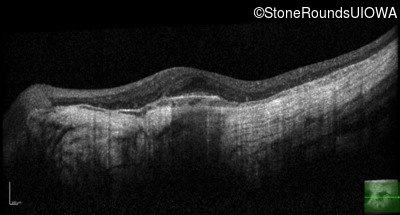

Optical Coherence Tomography - Right - 20/40 -2

Exemplar / OCT Stack